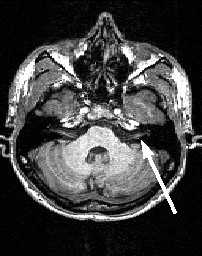

Кзади от моста и продолговатого мозга расположен мозжечок . Со стволом мозга он соединен верхней, средней и нижней ножками мозжечка. Состоит мозжечок из срединно расположенного червя и парных полушарий.

МРТ головного мозга. Аксиальный срез. Мозжечок (CV- червь мозжечка, CH - полушарие мозжечка).